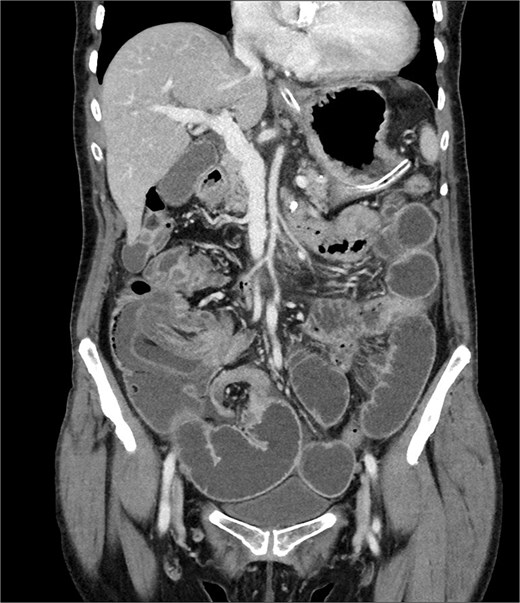

A 76-year-old female patient presented to the emergency department with abdominal pain and vomiting. A standard radiography (Fig. 1) and a contrast-enhanced abdominal CT scan revealed an intestinal obstruction caused by intussusception of the terminal ileum into the cecum (Figs 2 and 3). Laboratory tests showed elevated C-reactive protein levels and leukocytosis. Her medical history was significant for bilateral carotid artery stenosis (under treatment with clopidogrel), mild obstructive sleep apnea syndrome, and hypertension.

The patient exhibited classical symptoms of bowel obstruction (abdominal pain and vomiting), confirmed by imaging studies. The elevation of inflammatory markers suggested a more advanced disease stage, possibly with localized inflammation or ischemia. The patient’s prior medical history did not directly influence the intussusception, but these comorbidities required careful perioperative management. The CT scan clearly demonstrated intussusception of the terminal ileum into the cecum, which is consistent with an ileocolic intussusception, a relatively common form in adults. Given the clinical and radiological findings, the patient underwent urgent laparoscopic right hemicolectomy with extracorporeal anastomosis.

Intussusception is described as the telescoping of one bowel segment with its mesenteric fold into an adjoining bowel tract, causing venous congestion and blood supply reduction. Intussusception can occur anywhere along the small and large bowel. This condition in adults poses diagnostic and therapeutic challenges due to its rarity and the nonspecificity of symptoms. Most adult cases are associated with an underlying lesion, often neoplastic, benign [8] or malignant (metastatic lesions, lymphomas, and adenocarcinomas), which underscores the importance of surgical resection and histological analysis [5]. The use of contrast-enhanced CT has greatly improved the preoperative diagnosis of intussusception, allowing for early and accurate identification of the condition. CT scan shows a peculiar sign, described either as “target,” “bulls- eye,” or “sausage-shaped” lesion (Fig. 3). This pathognomonic sign can be identified at coronal and axial view [5]. This case emphasizes the need for a high index of suspicion in elderly patients presenting with bowel obstruction and nonspecific abdominal symptoms. Prompt surgical intervention, as performed in this case, is crucial to prevent complications such as bowel ischemia or perforation, which significantly increase morbidity and mortality. Moreover, in this case, an underlying potentially malignant evolving condition was discovered and removed. Given the patient’s overall clinical status and the urgency of the situation, the choice of surgical management was appropriate.